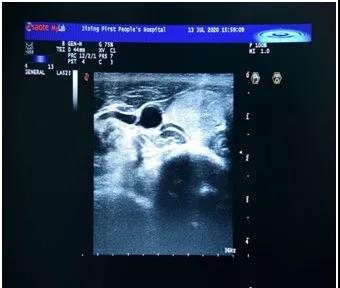

超声检查报告结果上有:

2级、3级、4a级、4b级、4c级、5级、6级?

超声医生根据什么进行分级的呢?

他们的分级依据如下图: